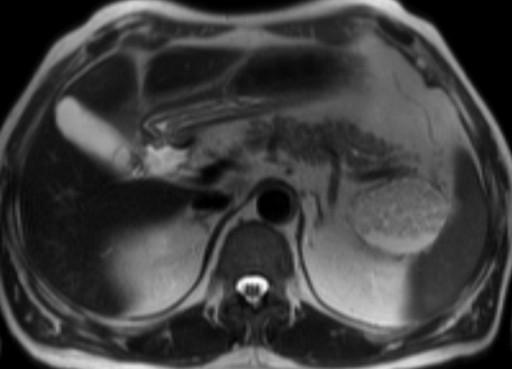

A 63-year-old man with a previous history of colon cancer, resected 3 years earlier, presented for a routine clinical follow-up. Physical examination and past medical history were unremarkable, except for an appendectomy at the age of 15. The patient had had a history of intermittent and mild left upper quadrant abdominal pain not associated with meals before a resection for colonic cancer; CA 19-9, CEA and amylase were unremarkable. There was no body weight loss or fever, and the patient had no previous history of pancreatitis. An abdominal ultrasound was performed which showed a 7 cm non homogeneous anechoic mass at the level of the pancreatic tail. An MR scan was subsequently obtained which confirmed the presence of a 7x4 cm lesion at the level of the pancreatic tail, close to the splenic hylum. This lesion showed a complex structure with multiple sub-centimeter nodules within it. In particular, the lesion was homogeneously hypointense on the pre-contrast T1-weighted MR images (Figure 1), showing a mild rim of enhancement after intravenous contrast administration while maintaining the hypointensity of the central core constant (Figure 2); on T2-weighted MR images, the pancreatic mass had a "cheerios-like" appearance, showing multiple small nodules with a central hypointensity and peripheral hyperintensity; a fluid-level was also present at the bottom of the lesion (Figures 3 and 4), most likely reflecting the inflammatory changes of the lesion. The patient subsequently underwent a distal pancreatectomy and splenectomy (due to the proximity of the lesion to the splenic hylum). Histological examination demonstrated the benign nature of the lesion consisting of a pancreatic lymphoepithelial cyst. The surface of the cyst was smooth, the lesion was filled with keratinous material and the walls were lined with stratified squamous epithelium which was surrounded by a layer of lymphoid tissue composed of small lymphocytes, plasma cells and germinal centers, without signs of atypia (Figure 5). The periphery was composed of normal pancreatic tissue. The postoperative course was uneventful and the patient was discharged from the hospital 10 days after the surgical intervention.

Figure 3. T2-weighted axial MR image showing a complex mass consisting of multiple sub-centimeter nodules, with a "cheerios-like" appearance, showing a central hypointensity with peripheral hyperintensity; a fluid-level is also present at the bottom of the lesion. |